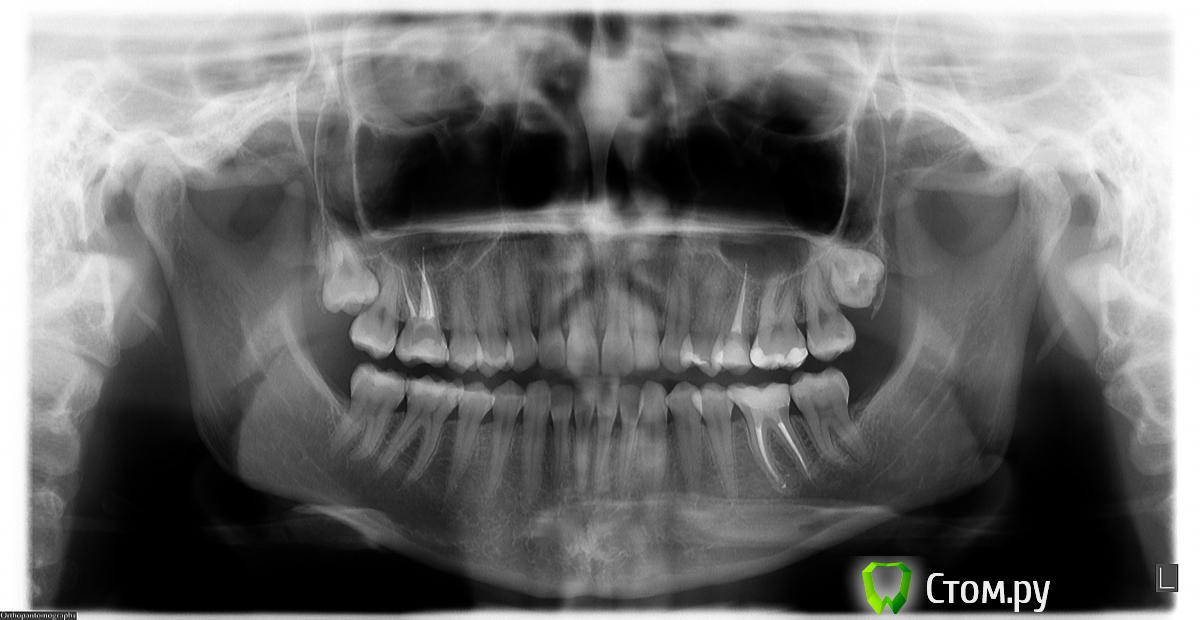

felicidade Опубликовано 15 февраля, 2015 Автор Поделиться Опубликовано 15 февраля, 2015 Добрый день, уважаемые доктора 36 зуб поживает нормально, ТТТ. У меня большая просьба: не могли бы вы сказать, если ли хоть минимальные признаки уменьшения кисты под ним после перепломбировки каналов (июль 2014)?Вот ОПТГ до перелечивания (апрель 2014). Тут уже октябрьская ОПТГ, а вот тут - свежайшая февральская (2015).Надеюсь, что если киста и не уменьшилась, то хоть кариесов новых нет А также, пользуясь случаем, ещё раз очень благодарю всех, кто поучаствовал в судьбе спасения зуба этим летом! Ссылка на комментарий

felicidade Опубликовано 6 ноября, 2015 Автор Поделиться Опубликовано 6 ноября, 2015 Здравствуйте! Это снова я Сегодня сделала контрольную ОПТГ (спустя 1г 3 мес после перепломбировки №36 и спустя 9 мес с момента последней ОПТГ). Эту не самую качественную ОПТГ я сделала вообще у ортодонта, т.к. у остальных стоматологов в нашем регионе запись новых пациентов на панорамный снимок+профилактический осмотр идёт самое раннее на январь 2016, а самое позднее - на май В общем, сейчас снова возьмусь за обзвон местных докторов, авось кто и примет меня пораньше с уже готовым снимком. А у меня, пока ищу стоматолога, снова нескромная просьба бегло оценить состояние челюсти: в апреле я наконец-то удалила верхние ретинированные зубы мудрости, ну, и, как всегда, у меня паническая боязнь вторичного кариеса под пломбами.. Всем ещё раз спасибо и хороших выходных! Ссылка на комментарий

felicidade Опубликовано 7 февраля, 2017 Автор Поделиться Опубликовано 7 февраля, 2017 (изменено) Добрый день, уважаемые господа стоматологи Вчера была на профилактической чистке зубов, заодно попросила сделать ОПТГ . Стоматолог сказал, что всё нормально - если не сложно, подтвердите или опровергните его мнение, пожалуйста Спасибо заранее! Изменено 7 февраля, 2017 пользователем felicidade Ссылка на комментарий